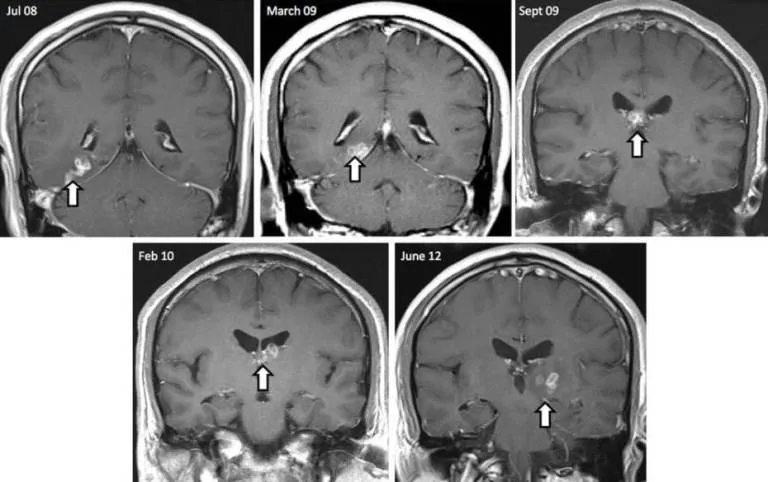

Con sán đã xuất hiện trong hình chụp não bộ của ông Donnelly từ khá lâu.